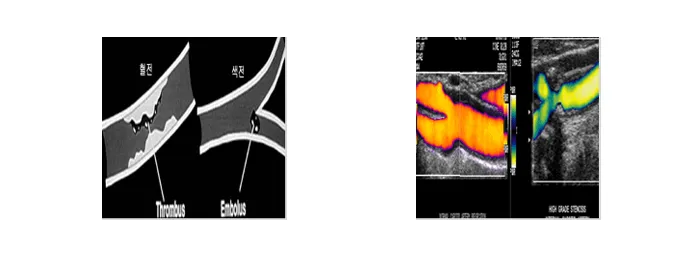

혈역학적인 불안정으로 인해 발생하는 동맥류나 가성동맥류는 색전술 치료가 시행됩니다.